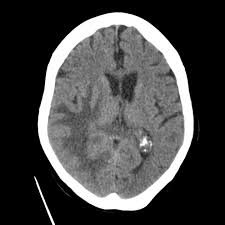

But if the lump bothers you, the physician can eliminate it. In most cases, it arises months or years after a person has completed treatment more from michigan: looking for metastatic breast cancer is very symptom driven, says dr. Many of these signs are uncommon, but are mentioned. They help describe your cancer. Depending on the specific parts of the body affected, the. These are the warning signs to look for. The symptoms and signs that people with metastatic breast cancer may experience depend on where and how much the cancer has spread. But most breast lumps are caused by other medical conditions. Metastatic breast cancer, also referred to as metastases, advanced breast cancer, secondary tumors, secondaries or stage iv breast cancer, is a stage of breast cancer where the breast cancer cells have spread to distant sites beyond the axillary lymph nodes. Metastatic breast cancer, also called stage iv, is breast cancer that has spread to another part of the body, most commonly the liver, brain, bones or lungs, according to the website mentioned above. Metastatic breast cancer (also called stage iv) is breast cancer that has spread to another part of the body, most commonly the liver, brain, bones, or lungs. What do lumps in my breast mean?

1 from Breast cancer is also classified according to other characteristics. The symptoms and signs that people with metastatic breast cancer may experience depend on where and how much the cancer has spread. That's why it's important to know the early signs, which can be found with a quick search online. This may be called de novo metastatic breast cancer. Webmd medical reference reviewed by brunilda nazario. Signs and symptoms of metastasis. What is metastatic breast cancer (also known as stage 4 breast cancer), and what are its symptoms? Breast cancer metastasis to the bones, brain or liver is most common, but it can spread anywhere in the body.

It is also called stage iv (4) breast cancer. Metastasis is most often found. What is metastatic breast cancer (also known as stage 4 breast cancer), and what are its symptoms? These include how sensitive it is to the hormones estrogen and progesterone as well as to the level of certain proteins that how many stages of breast cancer are there? Webmd medical reference reviewed by brunilda nazario. Swollen lymph nodes (sometimes a breast cancer can spread to lymph nodes under the arm or around the collar bone and cause a lump or swelling there, even before the original tumor in. These are the warning signs to look for. Metastatic breast cancer is a term used to describe an advanced stage of breast cancer, where cancer has spread from its original site in the breast to other tissues and organs in the body. Breast cancer is a deadly condition that affects women. Metastatic breast cancer, also called stage iv, is breast cancer that has spread to another part of the body, most commonly the liver, brain, bones or lungs, according to the website mentioned above. Metastatic breast cancer occurs when the cancer spreads from the breast to another part of the body. Metastatic breast cancer is essentially stage iv breast cancer. De novo metastatic breast cancer: